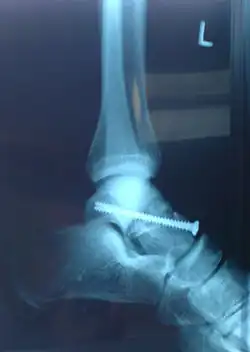

Frakturen bei Menschen

Knochenbrüche (Frakturen) des Sprungbeins sind sehr selten und machen nur 0,32 % aller Knochenbrüche und nur 3,4 % aller Brüche am Fuß aus. Bei Kindern kommen Sprungbeinbrüche quasi nicht vor. Ursächlich sind in der Regel Stürze aus großer Höhe oder Unfälle mit hoher Energie. Die ersten Fallserien wurden während der Weltkriege beschrieben und betrafen vor allem Piloten, die abgesprungen waren, und Fallschirmspringer, woher noch der Name aviator’s astragalus (Flieger-Sprungbein) herrührt.[9]

Am häufigsten sind die Talushalsbrüche zwischen dem distal gelegenen Taluskopf und der proximalen Talusrolle. Hierzu bedarf es meist einer forcierten Dorsalextension des Fußes, meist kombiniert mit einer Supinations- oder Pronationsbewegung (weshalb begleitende Knöchelbrüche nicht selten sind). Für die Talushalsbrüche wird sehr oft die Einteilung nach Hawkins genutzt:

Die Behandlung eines Knochenbruchs des Sprungbeins richtet sich nach der Lokalisation und Schwere der Fraktur. Bei einem Bruch ohne Verlagerung der Bruchenden stellt man den Fuß meist in einem Unterschenkel-Gips ruhig. Sind die Bruchenden verlagert (disloziert), kommt zumeist eine operative Methode (Osteosynthese) zum Einsatz. Die Gefahr einer Durchblutungsstörung mit nachfolgender Osteonekrose vor allem des Taluskörpers ist bei verschobenen oder mehrfragmentären Frakturen sehr groß, daher ist eine lange Entlastungsphase nach der Operation nötig. Vor allem bei Snowboardern kann es zu einer Fraktur des Processus lateralis tali kommen, die als Snowboarder’s Ankle bezeichnet wird.